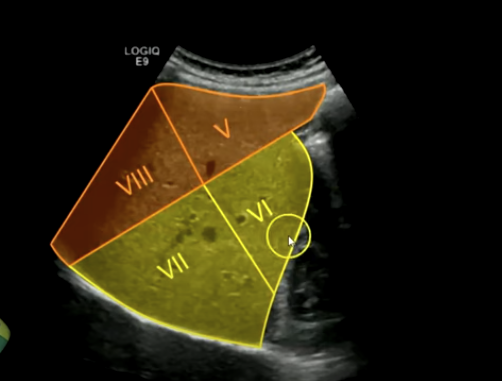

Right Hemi Liver:

Segments five, six, seven, and eight. These segments are supplied by the right hepatic artery and portal vein branch.

Right Hepatic Vein:

Separates segments seven and six from eight and five. The hepatic veins drain directly into the IVC.

Kidney (lateral view): Segments five, eight, six, and seven. The right kidney is located inferior and lateral to the right lobe of the liver.

Kidney (far lateral): Segments five, six, seven, and eight.

Superior segment of the right lobe (transverse): Hepatic veins, segments four a, eight, and seven.

Right hepatic vein separates eight from segment seven.